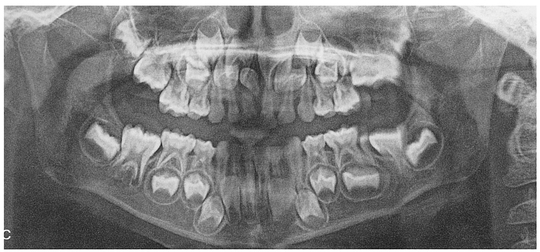

6年生~中1頃

すべての永久歯がおおかた萌出完了します。 その時点で、顎に上手に収まっていますか?八重歯の心配はありませんか? 咬み合わせは大丈夫そうですか?

なお、中学生時期に萌出完了する第2大臼歯(別名:12歳臼歯。親知らずではありませんよ)の生え方も、ムシ歯や将来の咬み合わせに大きく影響します。ここも実は隠れたチェックポイントです。